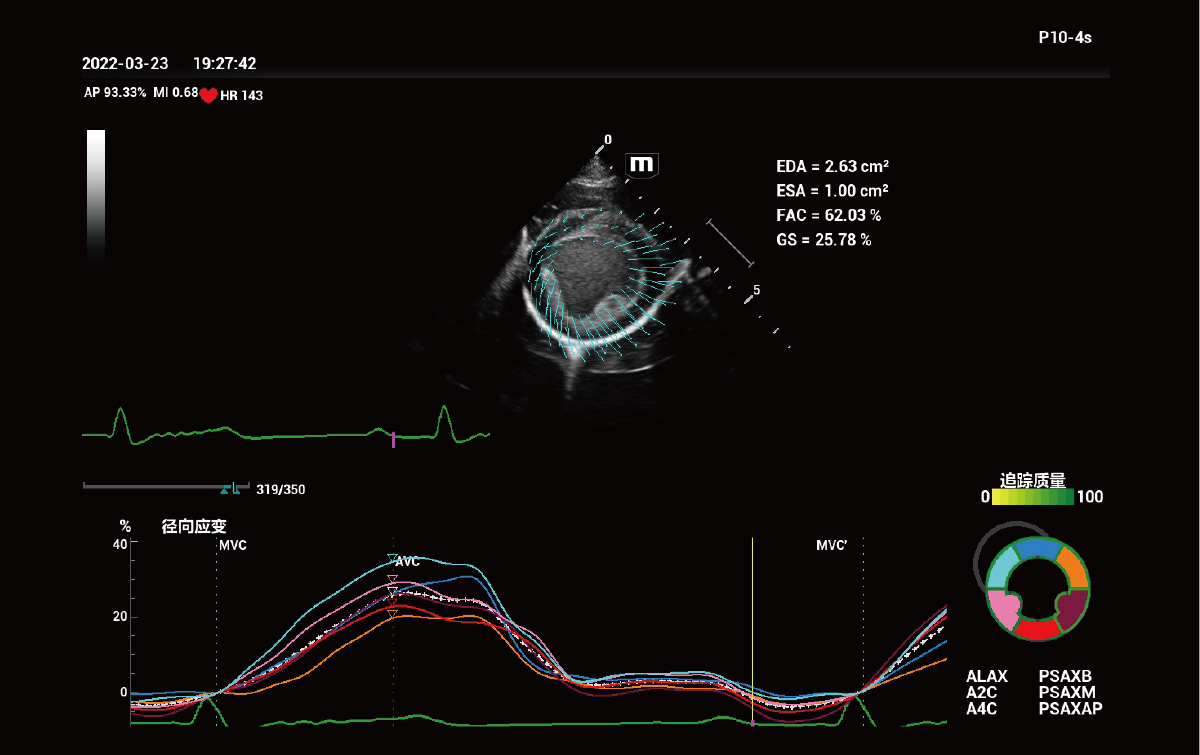

Evaluación del movimiento miocárdico independiente del ángulo – TT QA

El seguimiento de tejidos con análisis cuantitativo (TT QA) rastrea el movimiento del miocardio mediante la detección de patrones de motas 2D y proporciona una evaluación precisa e independiente del ángulo del movimiento del miocardio.